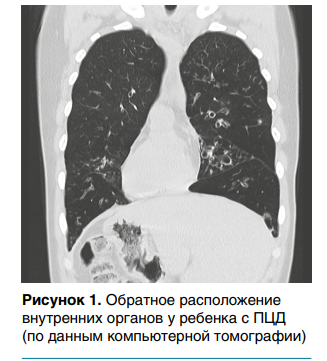

У части детей с ПЦД определяется обратное расположение внутренних органов, что в сочетании с бронхоэктазами и хроническим воспалением придаточных пазух носа исторически получило название синдрома Картагенера (синдрома Зиверта — Картагенера), который встречается у 35–55 % детей (рис. 1).